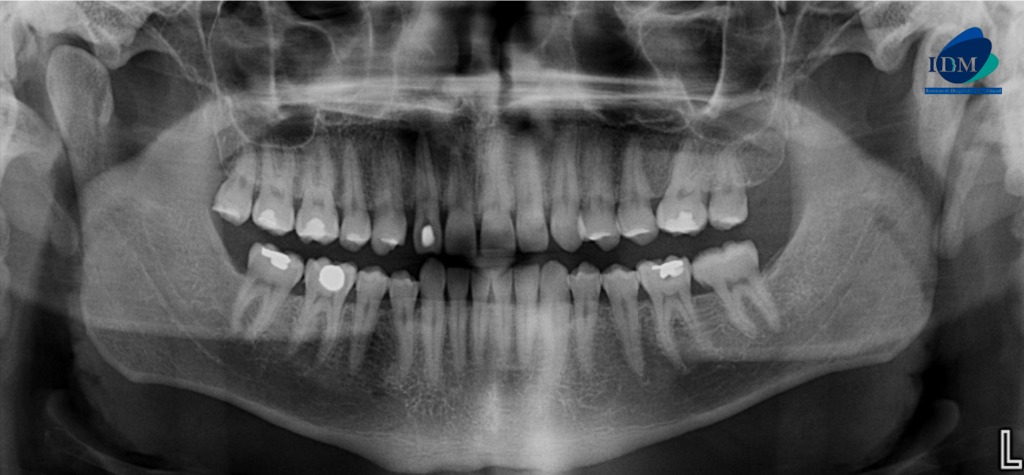

Radiografia Panorámica

A la evaluación de la radiografía panorámica se observa la neumatización de ambos senos maxilares, la presencia de placa cervical mineralizada, atrición de piezas dentarias anteriores y múltiples restauraciones coronarias. La pieza 22 presenta material restaurador en cara libre y un trazo radiolúcido de forma vertical paralelo al conducto pulpar, así también se observa un proceso osteolítico periapical parcialmente corticalizado.